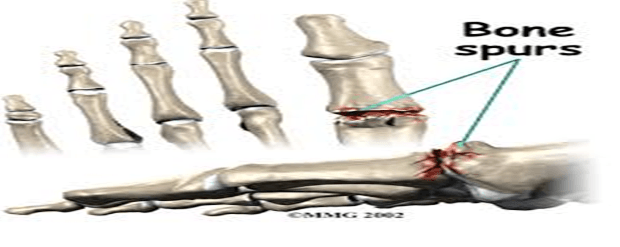

the degenerative disorder known as hallux rigidus, or arthritis of the big toe joint, is characterised by stiffness, inflammation, pain, and…